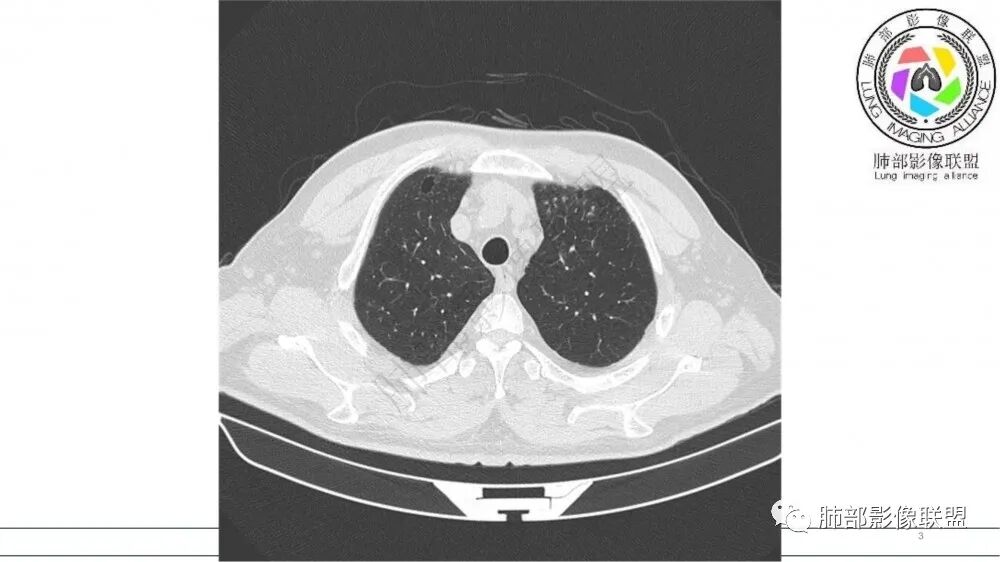

【每日晨读】上肺有强化的“指套征”

病例资料

资料拓展-指套征

指套征:是影像征象,胸部平片表现为手指状密度增高影,以肺门为中心呈放射状分布,CT显示扩张支气管内低密度黏液栓形成或实性病变,呈管状、树枝状或卵圆形密度增高影;支气管扩张伴近端梗阻时,扩张支气管内部黏液分泌物不能排出而形成。可以伴随远端空气潴留征、阻塞性炎症。